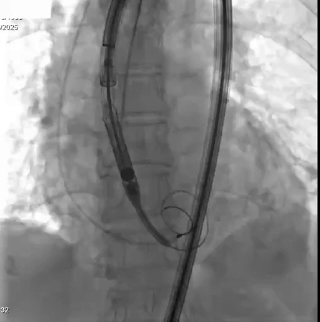

二、手术关键步骤:

输送器跨过瓣膜,定位件入窦

瓣膜释放